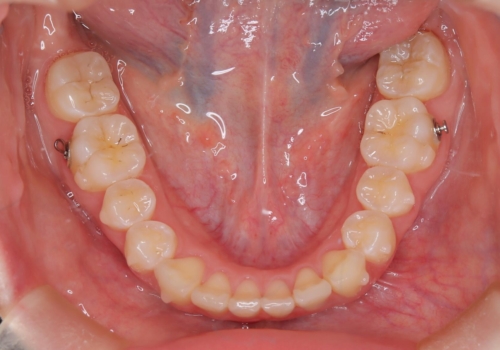

前歯のガタつきを治したい 翼状捻転マウスピース矯正

- 上顎前歯の突出、がたつき(翼状捻転)を主訴に来院されました。当院では総合歯科医療が可能であるため、矯正前処置として虫歯治療・歯周治療、親知らず抜歯を施行しました。その後、非抜歯かつ口元が出ないようなマウスピース治療を行いました。仕事柄、1日の装着時間が短くなってしまう時期もありましたが、患者様と相談しながら問題なく終了しています。

基本的に1日20時間、1週間に1枚ペースでご自身で交換し使用していただきます。会食等により1日の装着時間が短くなってしまうような場合は、1枚当たりのマウスピース使用日数を延ばすように指示をしております。